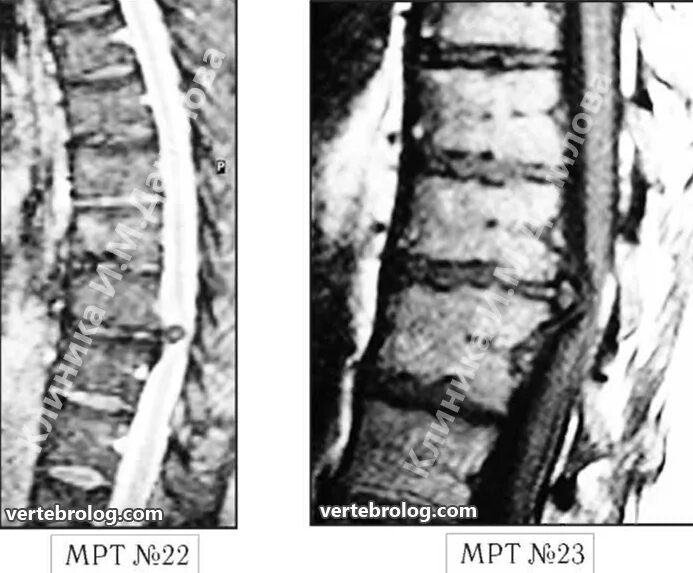

Каудальная миграция грыжи диска